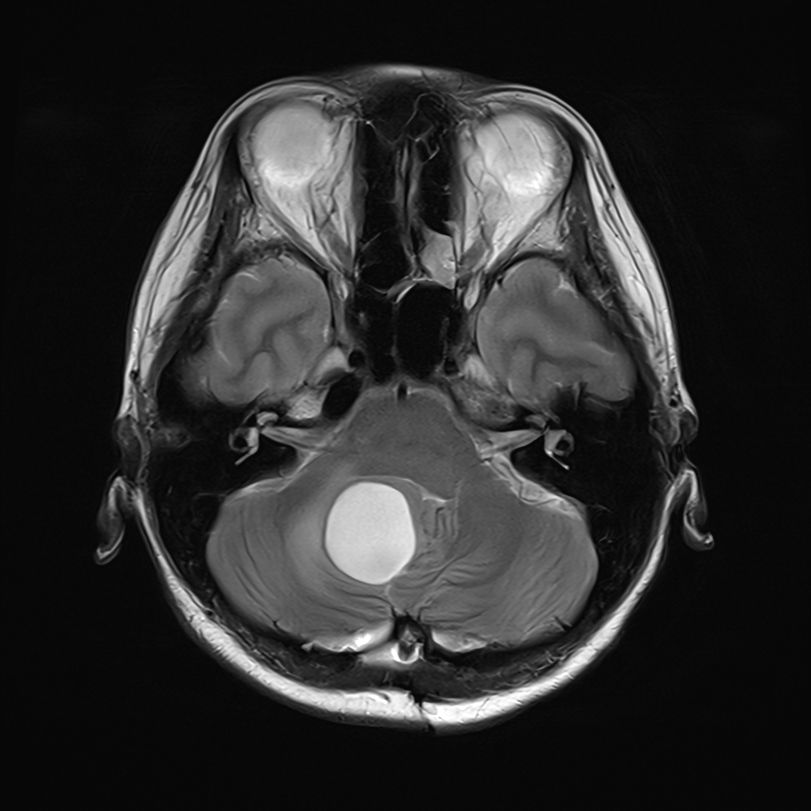

右小脳腫瘍

摘出術

北野